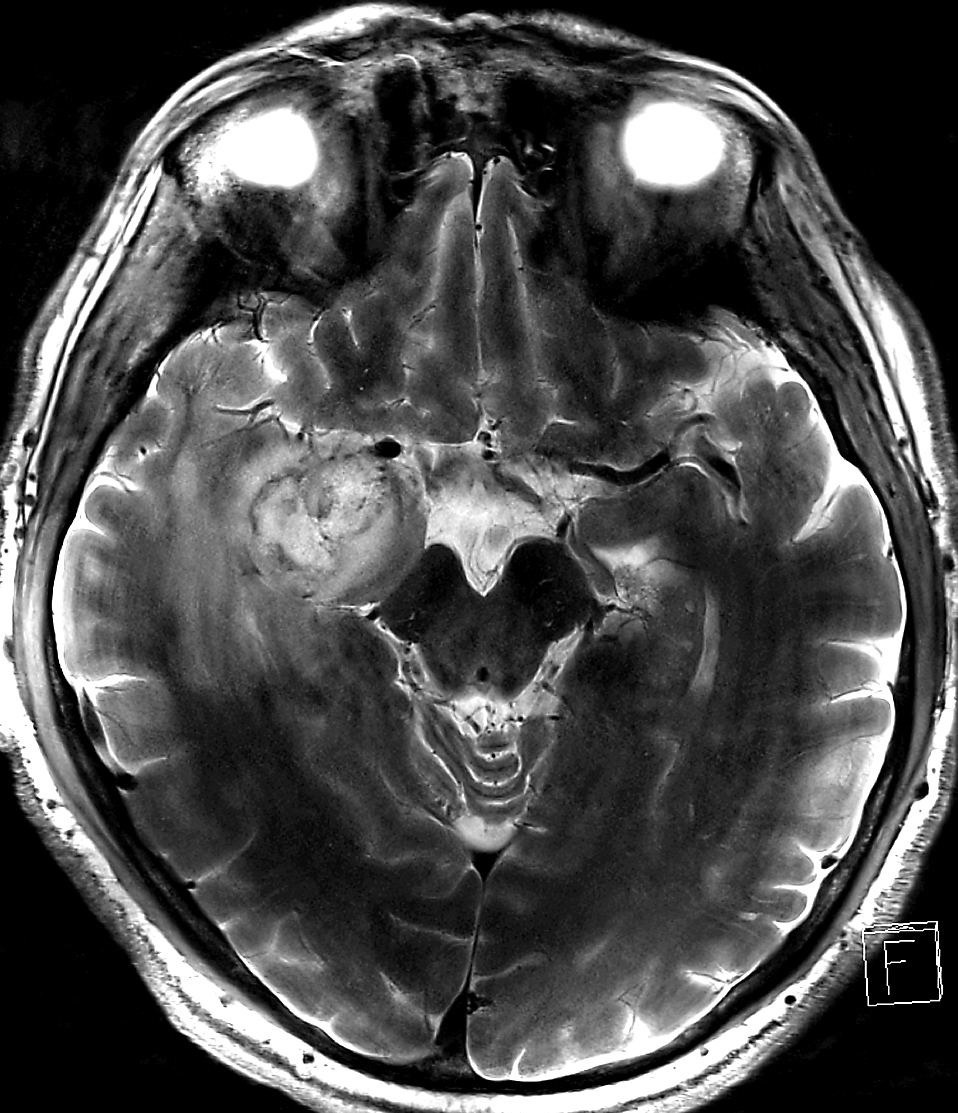

The initial diagnosis of a glioblastoma is often made with magnetic resonance imaging (MRI) which provides images with an excellent contrast between the tumor, the surrounding edema, and the adjacent normal brain tissue. Imaging of blood vessels is typically not part of the MRI exam, because the tiny and immature blood vessels of the tumor are difficult to detect with MRI. ‘With sub-millimeter MR angiography at very high magnetic fields of 7T we were able to see vessels surrounding the tumor’, says Michael Bock, former head of the high-field MRI at the DKFZ, and now professor for experimental radiology in Freiburg. ‘As part of the translational work at the DKTK, we wanted to bring this technology into clinical use.’ Irina Mader, professor for neuroradiology in Freiburg, adds: ’And this means: MRI field strengths of 3 Tesla and less.’

After careful optimization of the MR imaging parameters the team could detect the tumor vascu-lature also in a clinical setting. ‘However, seeing tumor blood vessels is not enough - the computer should automatically differentiate between tumor and normal vessels’, explains Maddalena Strumia, computer scientist in the team. ‘To achieve this, we first detected all vessels in the MR images, and then calculated their local orientation’. With this parameter normal, more straight blood vessels could be clearly separated from the curved tumor vessels. “With this software might be able to predict the success of a cost-intensive anti-angiogenic treatment at an early stage.” says Dr. Wilfried Reichardt.